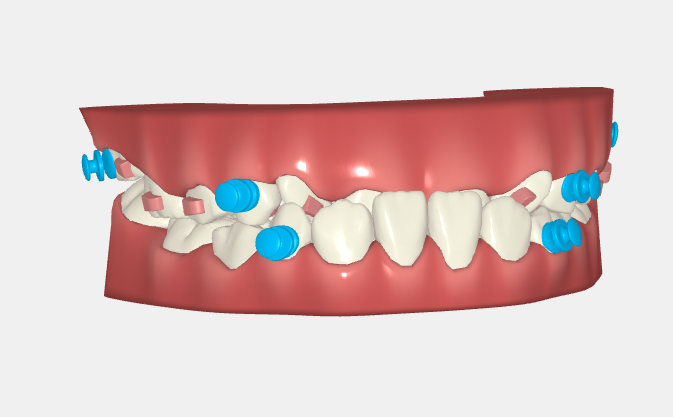

Retention & Expansion

Attachment Enhancing Retention and Reducing Removal Resistance

Designed to be strong in retention, with low resistance for removal and effective in reducing buccal inclination of teeth caused by dental expansion.

Treatment Plan

Elastic buttons used with anterior traction to correct anterior crossbite in pediatric cases.